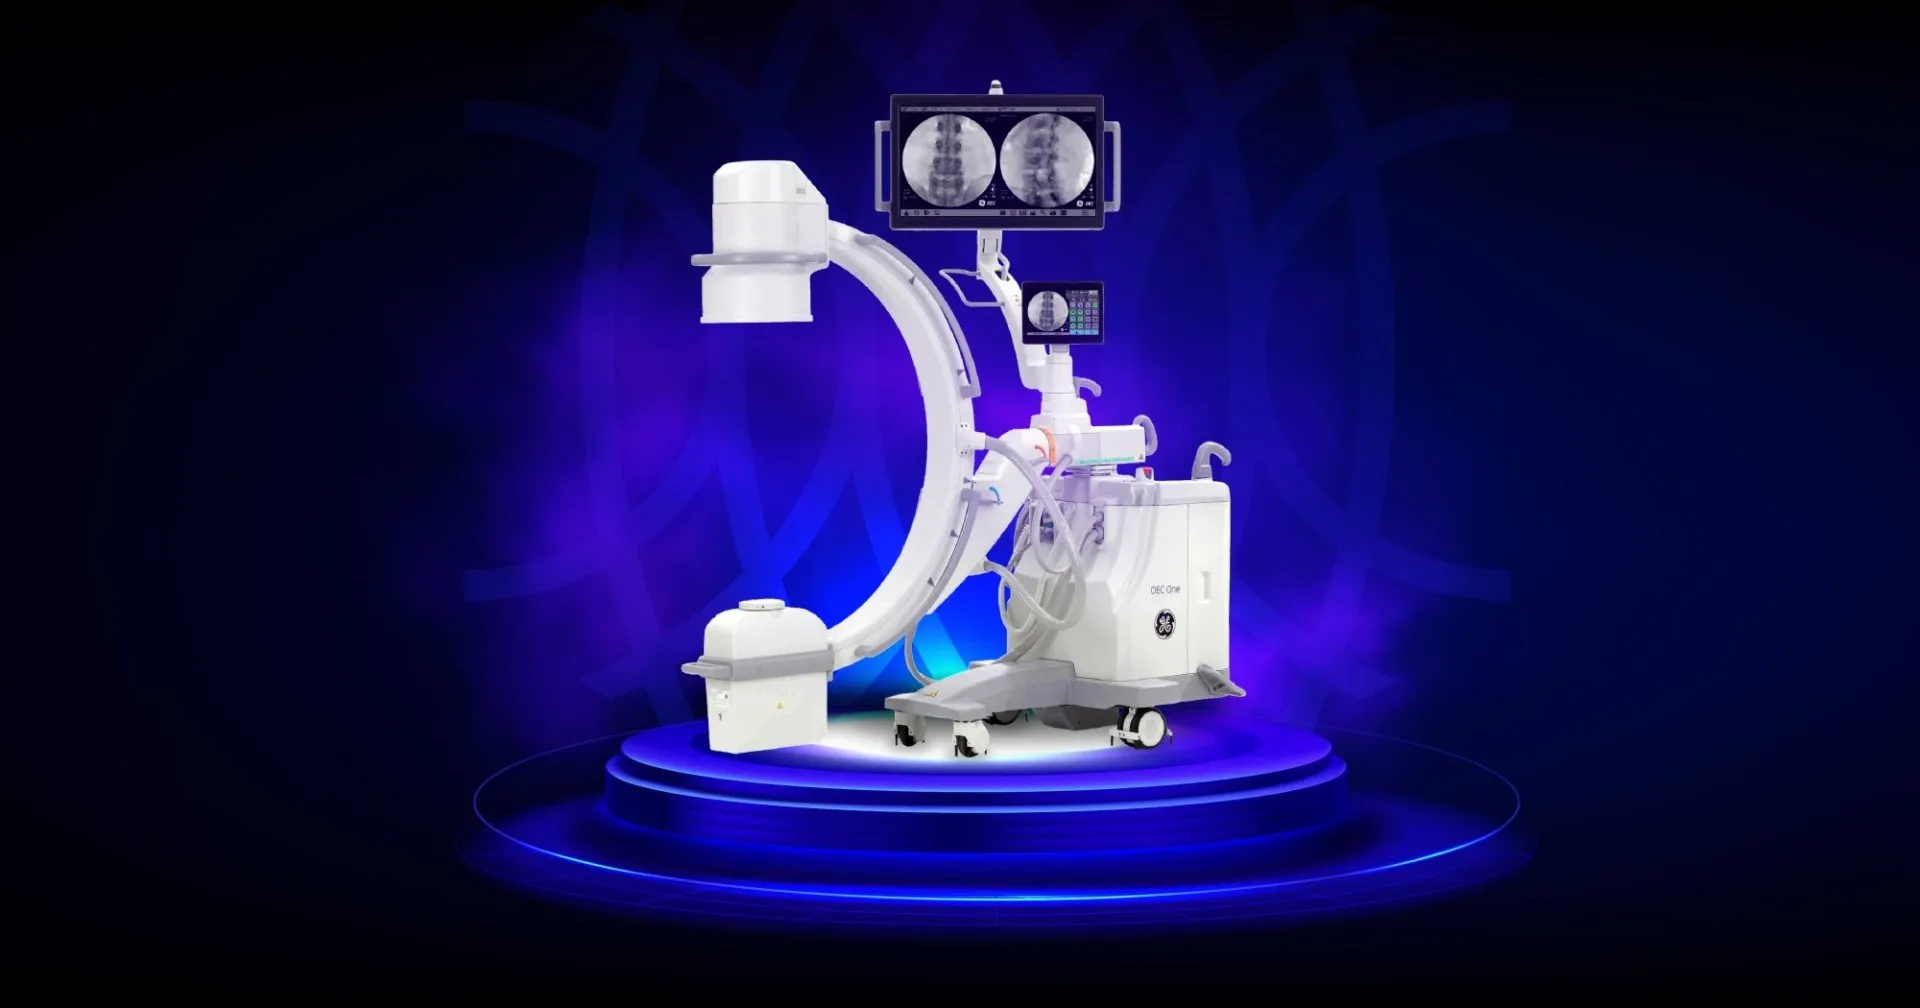

GE HealthCare OEC One — С-дуга, конструкция которой объединяет штатив и рабочую станцию, позволяет получить рентгеновские изображения самого высокого качества, а шарнирное крепление монитора вместе с сенсорным планшетом позволяет удобно позиционировать систему для комфортной работы. В качестве приемника в OEC One выступает усилитель рентгеновского изображения диаметром 9” с двумя полями увеличения 6”/4,5” и цифровой камерой на ПЗС-матрице с разрешением 1k*1k пикселей. Результаты исследования выводятся на широкоформатный дисплей 27”. Размер живого и референсного изображений составляют по 11,8” (30 см) каждый. В С-дуге предусмотрена функция дублирования живого изображения на сенсорную панель управления 10,1” (26 см).

Основные технические характеристики:

| Максимальная мощность генератора | 2,5 кВт |

| Тип рентгеновского излучателя | моноблок |

| Тип приемника рентгеновского изображения | УРИ 9 дюймов |

| Размеры рабочих полей приемника | Ø 9” / Ø 6” / Ø 4,5” |

| Конструкция системы | «всё в одном» включает в себя и штатив, и рабочую станцию |

| Глубина С-дуги | 66 см |

| Тип орбитального перемещения | ручное |

| 3D-визуализация | нет |

| Цифровая субтракционная ангиография | опционально |